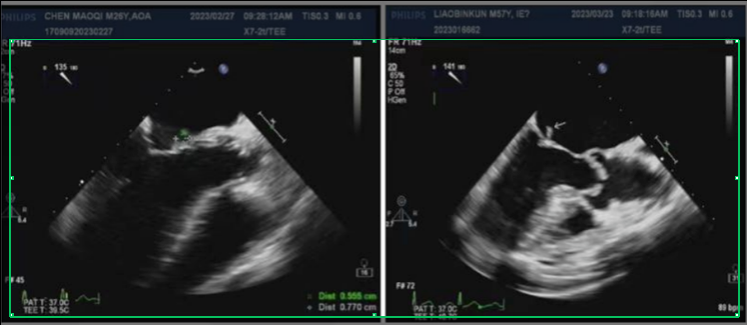

32 岁的王先生,因为拔牙后没注意护理,开始反复发烧,吃了退烧药也不管用,还总觉得心慌、没力气。医生怀疑是细菌通过拔牙伤口钻进了血液,流到心脏引发了感染,在经胸超声(TTE)检查时发现,他的主动脉瓣上,长了一个绿豆大小的「小疙瘩」——这是细菌形成的赘生物。同时还看到,因为这个小疙瘩的破坏,主动脉瓣关不严实,血液出现了反流。结合验血结果(查到了相同细菌),医生很快确诊了王先生病症属于「感染性心内膜炎」。

55 岁的李阿姨,患有多年风湿性心脏病,因最近突然出现高烧、呼吸困难,手指尖还长了紫红色的小疹子,她来到了医院, 医生通过经食道超声(TEE)检查后发现,她的二尖瓣后叶上,藏着一个米粒大小的「小疙瘩」,而且瓣膜已经被蛀出了一个小洞,还连累周围心肌长了个「小脓包」(瓣周脓肿)。原来,李阿姨也是得了感染性心内膜炎。

就像王先生的「米粒大赘生物」、李阿姨的「芝麻大隐藏病灶」,只有超声能直接看到这些感染的「证据」,结合验血结果,才能快速确诊,避免漏诊、误诊。

超声不仅能找「小疙瘩」,还能看它把瓣膜破坏到啥程度——是轻微反流,还是像李阿姨那样出现「破洞」「小脓包」,这些信息直接决定医生是选药物治疗,还是要做手术。

- 经胸超声(TTE):像王先生这样的初诊患者,先做这个「无创检查」——探头贴胸口,不痛不麻烦,能快速排查明显病灶,是首选的「初筛工具」。

- 经食道超声(TEE):李阿姨这样,经胸超声没发现问题但症状典型,或需要精准看瓣膜损伤、找隐藏病灶时,就用这个「高清工具」,能揪出 95% 以上的微小病灶。